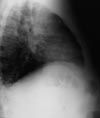

Chest radiographs are ordered.

Chest radiographic abnormalities are seen in up to half of all symptomatic patients. Typically, infiltrates are associated with ipsilateral hilar adenopathy. Peripneumonic pleural effusion may occur.

Diffuse pneumonia may also result from hematogenous spread. This is a rapidly progressive condition seen most commonly in immunocompromised patients; it may cause respiratory failure. Chest radiographs typically show a diffuse reticulonodular pattern throughout both lung fields.